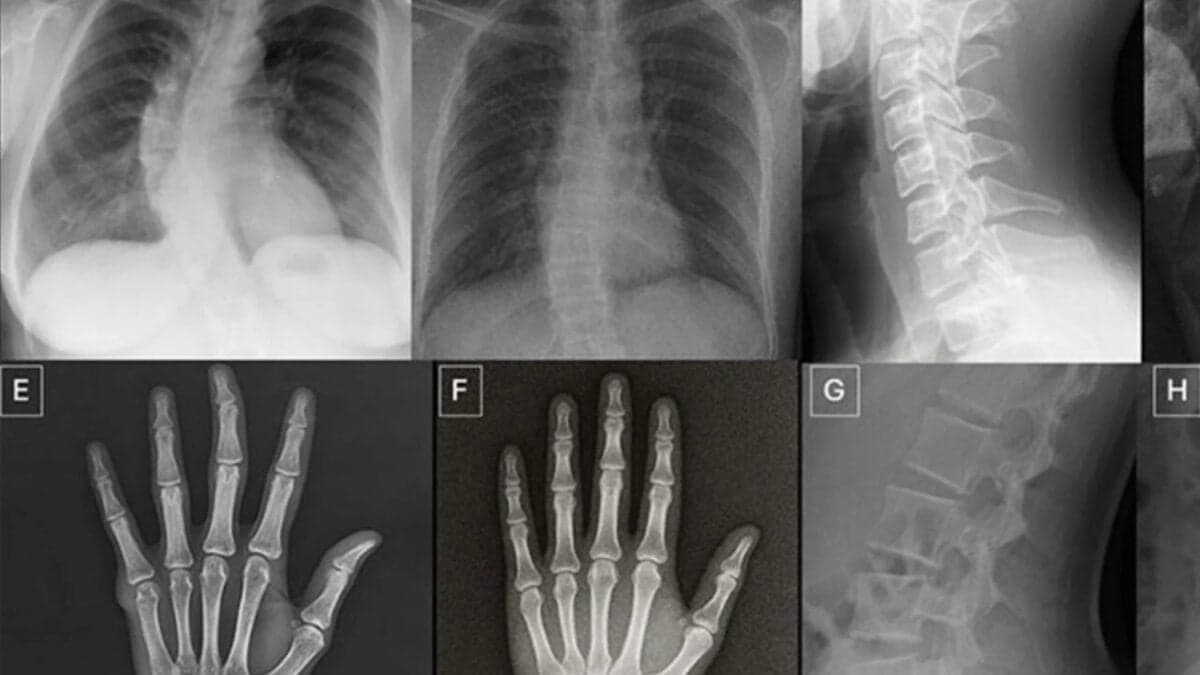

Tordjman espera que se continúe investigando este tema para desarrollar herramientas de detección y medidas educativas. “Las imágenes médicas falsas suelen parecer demasiado perfectas”, indicó. “Los huesos se ven muy suaves y lisos, las columnas vertebrales son excesivamente rectas y no lucen naturales, los pulmones aparecen exageradamente simétricos, los patrones de los vasos sanguíneos son excesivamente uniformes, y las fracturas se ven inusualmente limpias y consistentes”.